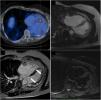

Right lower panel: Cardiac magnetic resonance imaging showing two rounded, well-defined intramyocardial high signal intensity lesions in T2-weighted sequences, at the medium and distal segments of the anterolateral wall (dark arrow). These two lesions showed isosignal intensity in T1-weighted images, and intense early (upper right panel, dashed arrow) and late (lower left panel, white arrows) gadolinium enhancement; Upper left panel: Positron emission tomography image shows increased 68Ga-DOTATOC uptake, further supporting the anatomic correspondence of these foci.

He had no cardiovascular symptoms. Clinical examination was unremarkable. The electrocardiogram showed sinus rhythm with no ST-T abnormalities. Transthoracic and transesophageal echocardiograms revealed no relevant structural or functional abnormality. Cardiac magnetic resonance imaging (MRI) showed two rounded, well-defined intramyocardial high signal intensity lesions in T2-weighted sequences, at the medium and distal segments of the anterolateral wall (Figure 1, right lower panel, dark arrow). These two lesions showed isosignal intensity in T1-weighted images, and intense early (Figure 1, right upper panel, dashed arrow) and late (Figure 1, left lower panel, white arrows) gadolinium enhancement. The anatomic correspondence between PET and cardiac MRI lesions led to diagnosis of cardiac metastasis of primary bronchogenic carcinoid.

A 46-year-old male was referred to the cardio-oncology clinic for comprehensive cardiovascular assessment. He had a medical history of bronchial carcinoid, having undergone left pneumonectomy 20 years earlier, and was diagnosed with stage IV disease (bone and liver metastasis). A 68Ga-DOTATOC positron emission tomography (PET) scan in July 2019 was notable due to two foci of abnormally high radionuclide uptake at the left inferolateral aspect of the cardiac silhouette (Figure 1, upper left panel).